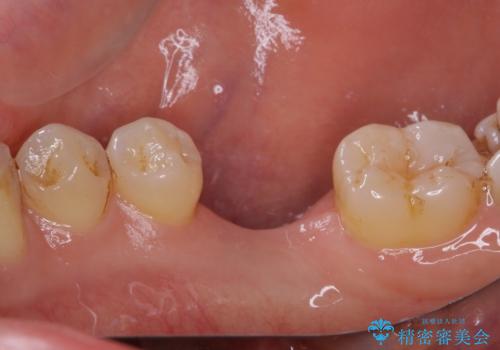

平日の昼間でもご来院可能とのことであったので、必要最小限の期間で治療を終えることができました。